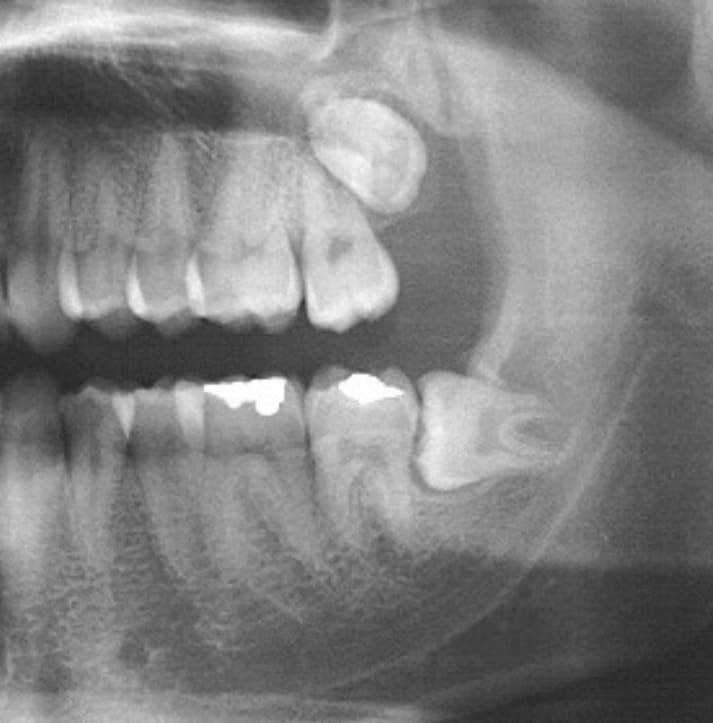

Avaliação clínica e por imagem

O dentista solicita radiografias ou tomografia para entender a posição dos sisos e planejar a extração.